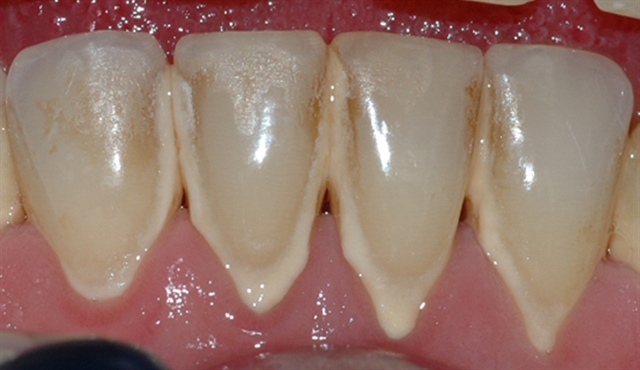

Bildet viser et tannsett med synlig tannsten og misfarging.